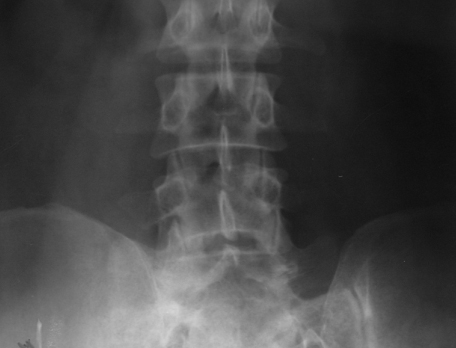

Figure 8: (a) Sclerotic myeloma – diffuse sclerosis of all the lumbar vertebrae. (b) Sclerotic lesion in the femur in Poems syndrome.